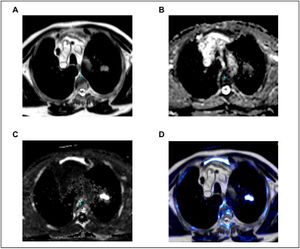

The Impact of Diffusion-Weighted MRI on the Definition of Gross Tumor Volume in Radiotherapy of Non-Small-Cell Lung Cancer

Publication: PLoS One. 2016 Sep 9;11(9):e0162816. PMID: 27612171 | PDF Authors: Fleckenstein J, Jelden M, Kremp S, Jagoda P, Stroeder J, Khreish F, Ezziddin S, Buecker A, Rübe C, Schneider GK. Institution: Department of Radiotherapy and Radiation Oncology, Saarland University Medical Center, Homburg, Germany. Background/Purpose: The study was designed to evaluate diffusion-weighted magnetic resonance imaging (DWI) vs. PET-CT of the thorax in the determination of gross tumor volume (GTV) in radiotherapy planning of non-small-cell lung cancer (NSCLC). MATERIALS AND METHODS: Eligible patients with NSCLC who were supposed to receive definitive radio(chemo)therapy were prospectively recruited. For MRI, a respiratory gated T2-weighted sequence in axial orientation and non-gated DWI (b = 0, 800, 1,400 and apparent diffusion coefficient map [ADC]) were acquired on a 1.5 Tesla scanner. Primary tumors were delineated on FDG-PET/CT (stGTV) and DWI images (dwGTV). The definition of stGTV was based on the CT and visually adapted to the FDG-PET component if indicated (e.g., in atelectasis). For DWI, dwGTV was visually determined and adjusted for anatomical plausibility on T2w sequences. Beside a statistical comparison of stGTV and dwGTB, spatial agreement was determined with the "Hausdorff-Distance" (HD) and the "Dice Similarity Coefficient" (DSC). RESULTS: Fifteen patients (one patient with two synchronous NSCLC) were evaluated. For 16 primary tumors with UICC stages I (n = 4), II (n = 3), IIIA (n = 2) and IIIB (n = 7) mean values for dwGTV were significantly larger than those of stGTV (76.6 ± 84.5 ml vs. 66.6 ± 75.2 ml, p<0.01). The correlation of stGTV and dwGTV was highly significant (r = 0.995, p<0.001). Yet, some considerable volume deviations between these two methods were observed (median 27.5%, range 0.4-52.1%). An acceptable agreement between dwGTV and stGTV regarding the spatial extent of primary tumors was found (average HD: 2.25 ± 0.7 mm; DC 0.68 ± 0.09). CONCLUSION: The overall level of agreement between PET-CT and MRI based GTV definition is acceptable. Tumor volumes may differ considerably in single cases. DWI-derived GTVs are significantly, yet modestly, larger than their PET-CT based counterparts. Prospective studies to assess the safety and efficacy of DWI-based radiotherapy planning in NSCLC are warranted. |

Development of a Nomogram Combining Clinical Staging with 18F-FDG PET/CT Image Features in Non-small-cell Lung Cancer Stage I-III

Publication: Eur J Nucl Med Mol Imaging. 2016 Jul;43(8):1477-85. PMID: 26896298 | PDF Authors: Desseroit MC, Visvikis D, Tixier F, Majdoub M, Perdrisot R, Guillevin R, Cheze Le Rest, Hatt M. Institution: Nuclear Medicine, University Hospital, Poitiers, France. Background/Purpose: Our goal was to develop a nomogram by exploiting intratumor heterogeneity on CT and PET images from routine 18F-FDG PET/CT acquisitions to identify patients with the poorest prognosis. Methods: This retrospective study included 116 patients with NSCLC stage I, II or III and with staging 18F-FDG PET/CT imaging. Primary tumor volumes were delineated using the FLAB algorithm and 3D Slicer on PET and CT images, respectively. PET and CT heterogeneities were quantified using texture analysis. The reproducibility of the CT features was assessed on a separate test-retest dataset. The stratification power of the PET/CT features was evaluated using the Kaplan-Meier method and the log-rank test. The best standard metric (functional volume) was combined with the least redundant and most prognostic PET/CT heterogeneity features to build the nomogram. Results: PET entropy and CT zone percentage had the highest complementary values with clinical stage and functional volume. The nomogram improved stratification amongst patients with stage II and III disease, allowing identification of patients with the poorest prognosis (clinical stage III, large tumor volume, high PET heterogeneity and low CT heterogeneity). Conclusion: Intratumor heterogeneity quantified using textural features on both CT and PET images from routine staging18F-FDG PET/CT acquisitions can be used to create a nomogram with higher stratification power than staging alone. |